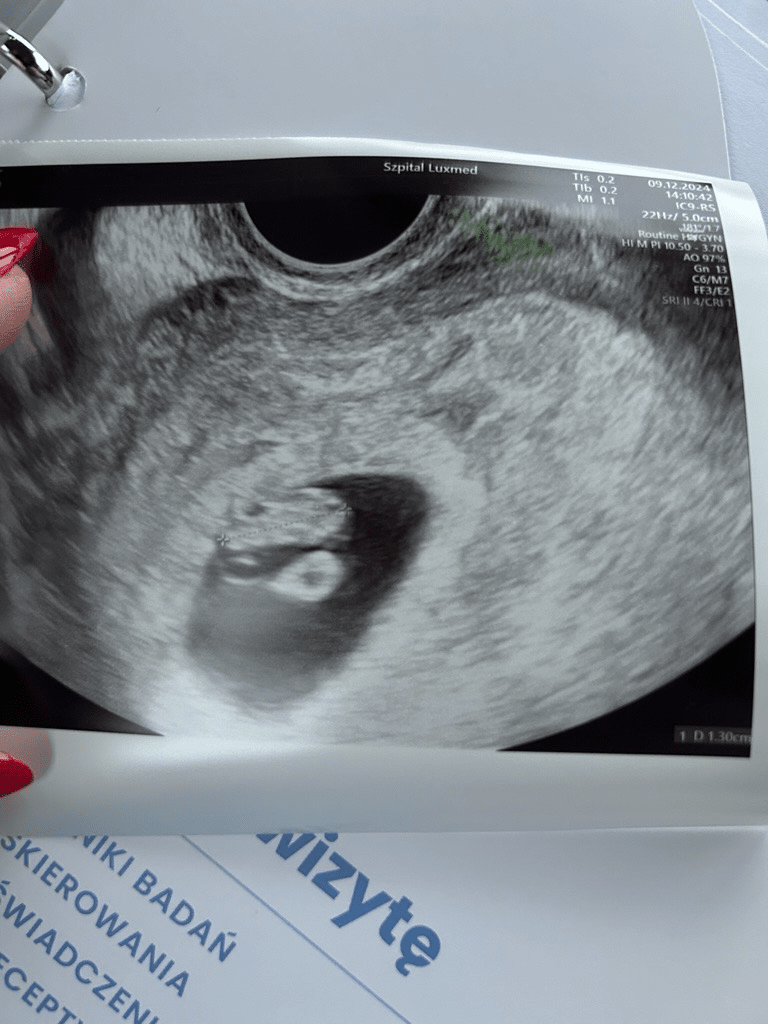

Poniżej zdjęcie z wczorajszego USG (7+4), serduszko pięknie bije.

Czy u Was też to ciałko żółte jest wciąż widoczne? Pytałam lekarza i powiedział, że na tym etapie to jest ok.